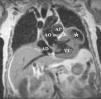

Seudoaneurisma ventricular izquierdo.

Left ventricular pseudoaneurysm